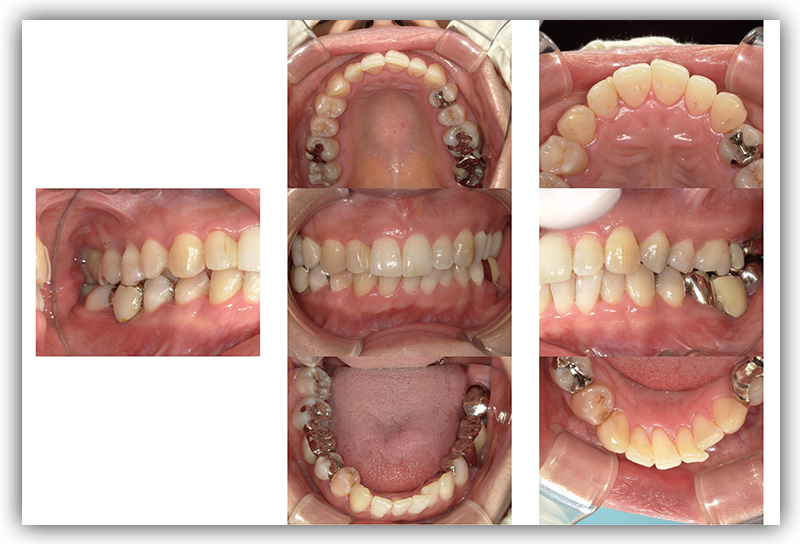

CASE_03

40代女性(インプラント)

- 患者さん情報(年齢・性別)

- 40代 女性

- 主訴

- 被せものをインプラントにしたい

- 治療箇所

- 2箇所

- 治療方法

- インプラント

- 費用

- 84万円

- 治療期間

- 約半年

- その治療によるリスク・副作用

-

- 治療期間がながい、外科的治療が必要

- 患者様の声